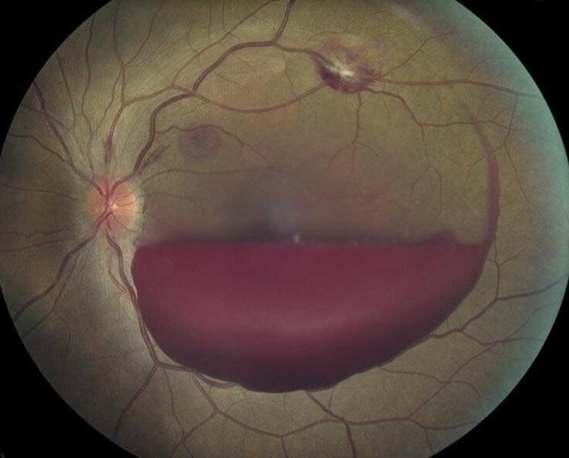

Como retinólogo, a menudo veo los devastadores efectos de la retinopatía diabética en mis pacientes. Esta enfermedad ocular es una complicación común y grave de la diabetes, y puede llevar a la ceguera si no se trata adecuada y oportunamente. Mi objetivo con este artículo es concienciar sobre la importancia de la detección temprana, el manejo adecuado de la diabetes y los tratamientos disponibles para la retinopatíadiabética.

¿Qué es la Retinopatía Diabética?

La retinopatía diabética es una condición que ocurre cuando el alto nivel de azúcar en la sangre daña los vasos sanguíneos en la retina, el tejido sensible a la luz en la parte posterior del ojo. Esto puede causar la formación de microaneurismas, hemorragias y, en etapas avanzadas, el crecimiento de vasos sanguíneos anormales que pueden llevar a una pérdida severa de visión incluso a la ceguera por desprendimiento de retinaoglaucomaneovascular.

Importancia de la Detección Temprana

Uno de los mayores desafíos que enfrentamos como retinólogos es la detección temprana de la retinopatía diabética. A menudo, los pacientes no experimentan síntomas en las primeras etapas de la enfermedad, lo que hace crucial que las personas con diabetes se sometan a exámenes o almológicos regulares. La detección temprana nos permite intervenir antes de que la enfermedad progrese y cause daños irreversibles a la visión.

Manejo de la Retinopatía Diabética

El manejo de la retinopatía diabética requiere un enfoque integral que incluya el control estricto de los niveles de glucosa en sangre y la presión arterial. Recomiendo a mis pacientes que colaboren

estrechamente con su equipo de atención médica para mantener sus niveles de glucosa dentro de un rango objetivo. Además, deben adoptar un estilo de vida saludable que incluya una dieta equilibrada y ejercicio regular

Tratamientos Disponibles

En cuanto a los tratamientos, la fotocoagulación con láser es una de las opciones más comunes y efectivas para tratar la retinopatía diabética. Este procedimiento utiliza láseres para mejorar la oxigenación de la retina evitando las complicaciones mencionadas. También hay medicamentos anti-VEGF que se inyectan en el ojo y pueden ayudar a reducir la formación de nuevos vasos sanguíneosanormalesymejorarlavisión.

En casos más avanzados, la cirugía vitreorretinal puede ser necesaria para reparar los daños causados por la retinopatía diabética proliferativa. Esta cirugía puede involucrar la eliminación del vítreo, el gel que llena el interior del ojo, para acceder y tratar las áreas dañadas delaretina.

Conclusión

La retinopatía diabética es una condición seria que puede tener un impacto devastador en la visión y la calidad de vida de las personas con diabetes. Como retinólogo, insto a todos mis pacientes y a la comunidad en general a tomar medidas preventivas y buscar atención o almológica regular La detección temprana y el tratamiento adecuado son fundamentales para preservarlavisiónymejorarlosresultadosalargoplazo Espero que este artículo te sea útil. ¿Hay algo más en lo quepuedaayudarte?

Dr. Daniel Belaunde Sánchez Cirujano O almólogo-Retinólogo

Céd. Prof. 3869064

Céd. Esp. 4371738

Citas: 9996 88 9393